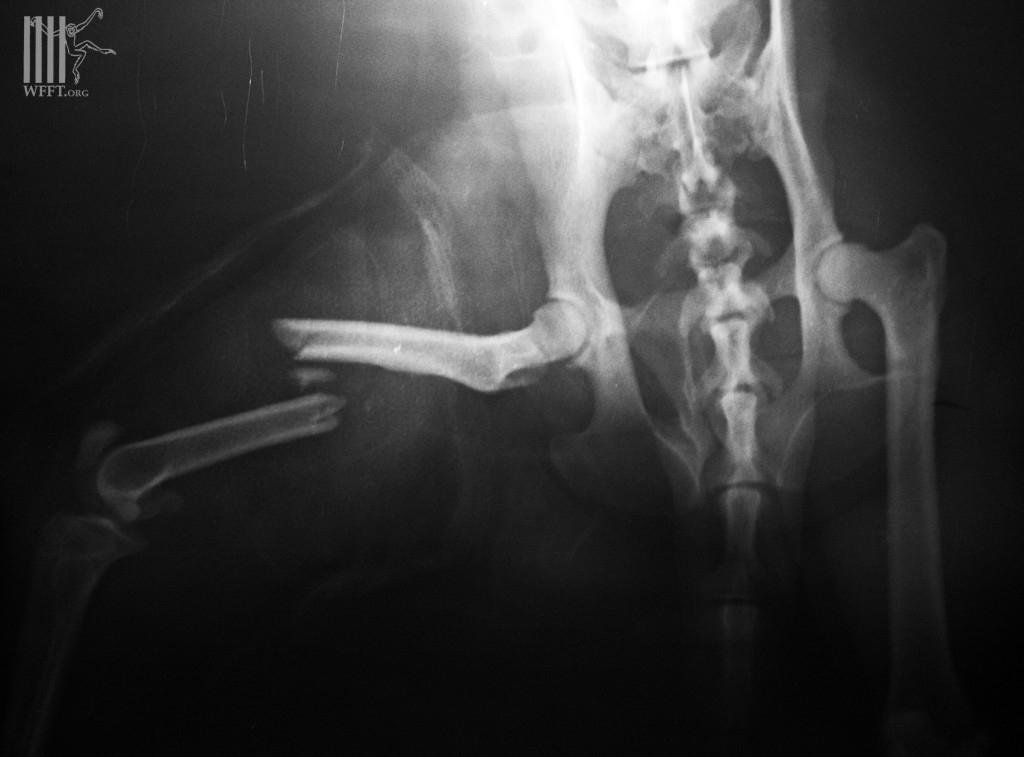

Bad luck for a long-tailed macaque “Mr Faifa”, but after all a happy ending. “Faifa” was climbing an electric pole in Petchburi city two weeks ago, when he got electrocuted and fell down from the 6 meter high powerlines. His bad luck didn’t end there with burning wounds, as he had bruises from the fall and even got hit by a passing motorbike, fracturing his leg…